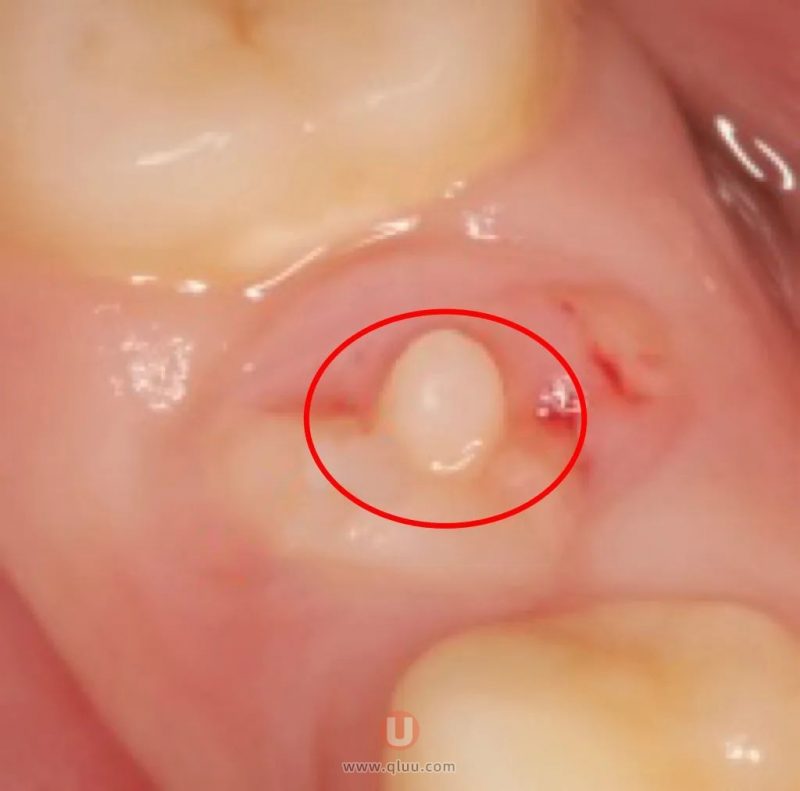

小朋友因牙龈反复肿包到我院就诊,检查发现在肿包的对应牙齿上,有一个突出的“小尖尖”。原来,他是因为畸形中央尖断裂导致牙龈反复肿包。

畸形中央尖是牙体发育畸形的一种,多见于下颌第二前磨牙,常为对称性发生,一般出现于9-12岁。表现在磨牙或磨牙中央窝处,或接近中央窝的颊尖三角嵴上突出一圆锥状的“小尖尖”,内有牙髓伸入,很易折断而继发牙髓和根尖周病。